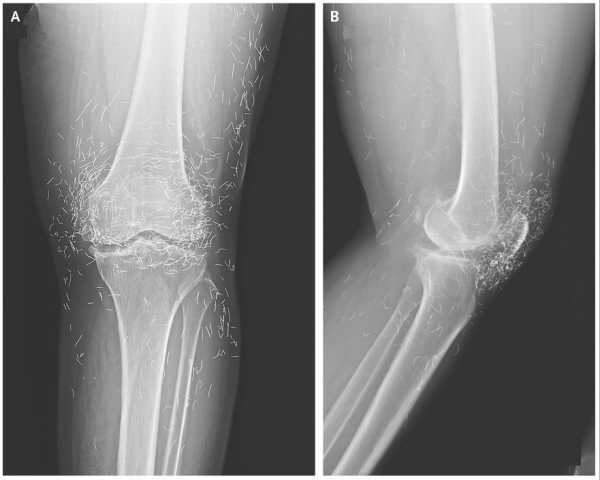

Комп'ютерна томографія грудної клітки чоловіка виявила кальцифіковані ділянки грудних м'язів, куди він раніше вводив олії для покращення м'язової маси. (Зображення надано: Markowska et al. BMC Nephrol 26, 476 (2025). (CC 4.0))

Чоловік загалом був стабільним, але медичний огляд показав помітні зміни в м’язах плеча та грудей, що відповідали порушенням, виявленим на сканах. Потім лікарі переглянули історію хвороби пацієнта, і він поділився важливою деталлю: приблизно 30 років тому він почав отримувати «невідомі внутрішньом’язові ін’єкції (ймовірно, що містять тестостерон)» у м’язи грудей та плечей для їх збільшення, згідно зі звітом про його випадок.

Аналізи крові показали, що рівень паратиреоїдного гормону, який контролює кальцій у чоловіка, був значно низьким, що виключає поширену гормональну причину високого рівня кальцію. У чоловіка також не було ознак прихованого раку в травному тракті, жодних відхилень при урологічному обстеженні та жодних ознак аутоімунного захворювання. Виключивши інші причини, медична бригада провела біопсію однієї з аномальних ділянок м'яза.

Діагноз: під мікроскопом м'яз був заповнений силіконополімерною речовиною на масляній основі та оточений щільними кальцієвими відкладеннями. Команда вчених дійшла висновку, що попередні ін'єкції чоловіка в м'язи, ймовірно, містили синтол, речовину, що складається переважно з олії, яка візуально «наповнює» м'язи, по суті, надуваючи їх, як водяні кульки.

У цьому випадку синтол викликав стійку реакцію на чужорідне тіло — організм, по суті, реагував на матеріал, який він не міг розщепити. З часом ця реакція призвела до рубцювання та кальцифікації, що призвело до накопичення великої кількості кальцію всередині м'яза. І зрештою цей кальцій потрапив у його кров.